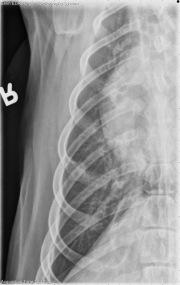

Today’s case is a 6 year old male Spaniel with previous amputation performed for left thoracic limb osteosarcoma. What are your findings?

The left thoracic limb is absent, and there are metallic staples in the soft tissues consistent with previous amputation. The cardiovascular structures are normal in size and shape. No abnormalities are seen in the pulmonary parenchyma, pleural space, or mediastinum. The first sternebra is radiolucent and irregular in appearance with subtle periosteal reaction. On the dorsoventral projection, there is expansion and lysis of the right 6th rib. These findings are confirmed on collimated projections. There is osteophyte production surrounding the right shoulder joint.

Osteosarcoma metastasis to the right 6th rib and first sternebra.